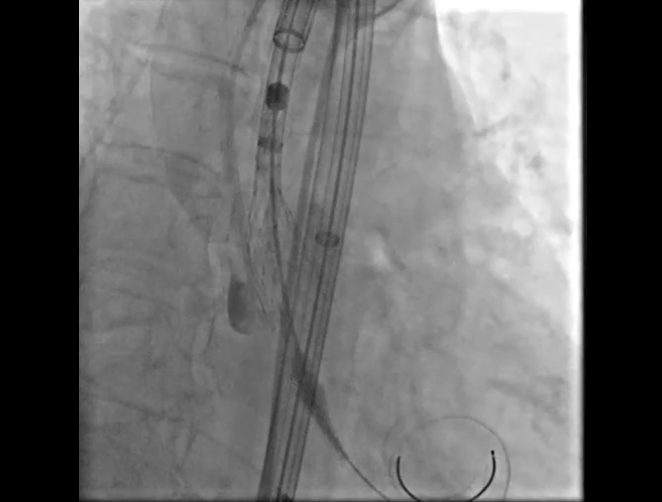

Step 5.瓣膜定位与释放:高起始位逐渐向下推送保持良好同轴性,无位移

Step 6.工作位观察:真实瓣环下方2mm,位置合适,决定释放,一次完成

Step 7.瓣膜脱钩:脱钩稳定无位移

Step 8.最终造影:真实瓣环下方3mm标准位,完全同轴,轻微反流,猪尾撤出后反流完全消失

Step 10.验证器械同轴性,完全同轴